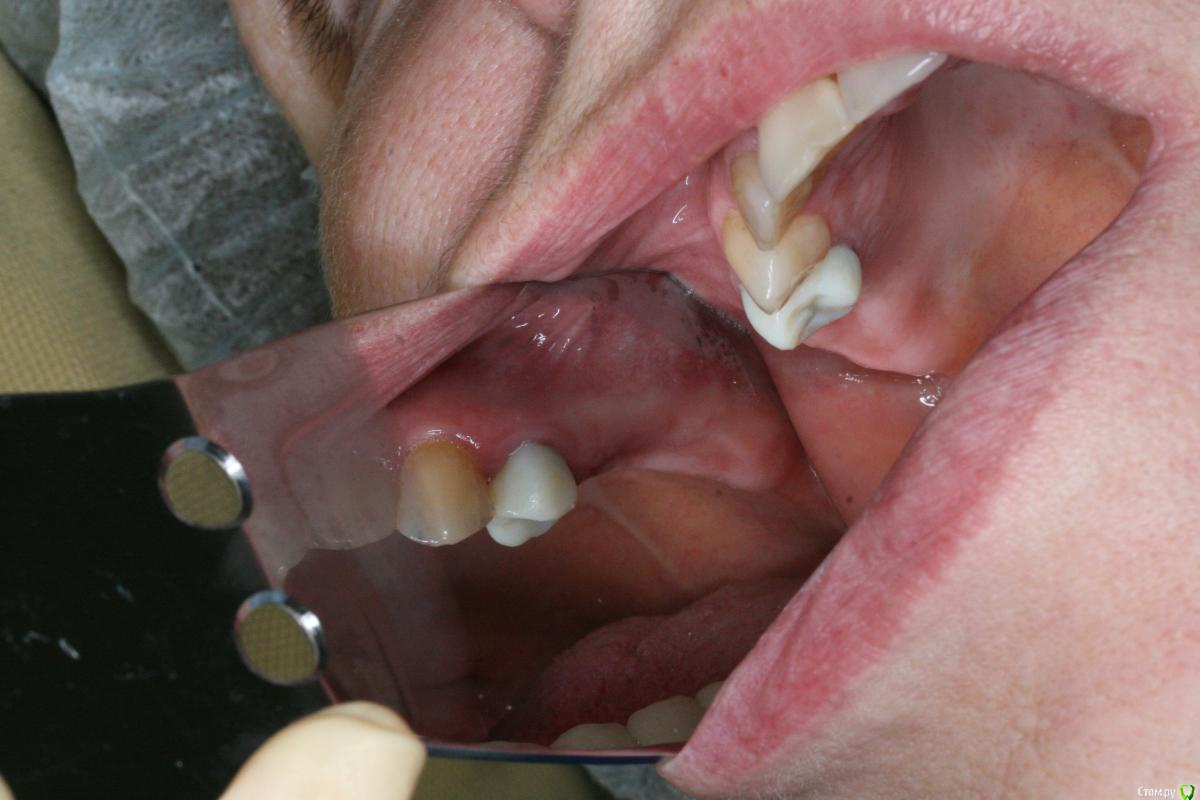

kamranchick Опубликовано 30 мая, 2017 Поделиться Опубликовано 30 мая, 2017 Добрый день. Дабы не плодить темы по тактике всяких утолщений продолжу здесь.Клкт через 6нед после удаления 1.7 Планирем синуслифт+импл в поз 1.7 1.5, Как бы вы поступили? Пойти крестально на синус в обл 15+ латерально окно для аспирации содержимого илисделать два окна выше/ниже иливообще отслаивать как при обычном ибо это не киста а полип все зависит от ваших манульных навыков, можно и аспирировать жидкость можно не аспирировать, я бы не аспирировал и пошел бы двух этапно, сначала синус, через 6 месяцев повторное кт и оценил бы ситуацию для последующей имплантации. и посмотрите может это все от 4 зуба, на мой взгляд целесообразно удалить зуб 4 и установить имплантат 4 - 6 так как в области 7 го зуба неровности, при выполнения синус лифтинга будут определенные риски, плюс на нижней челюсти длинный мост стоит, скорее всего не особо надежный Ссылка на комментарий